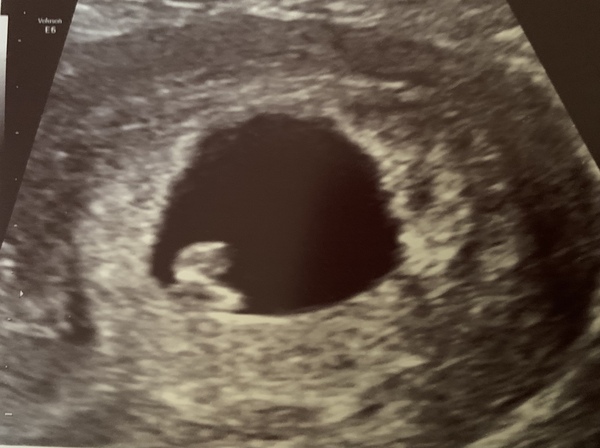

NightDreaming · 17/05/2021 11:38

Morning. Hope you are all feeling ok. Having felt rubbish for a few days had my first nausea over the weekend. Which wasn’t nice but tried to take it as a good sign.

This morning I had an early scan and I just wanted to share the good news with you all. Baby currently all seems fine. Measuring 7wks which is what we expected and we saw the heart beating ❤️. So relieved. I had a little cry. Having been trying 3 years with 3MC in a row these passed few weeks have seem so tense. Not out of the woods yet, but feeling on a more normal leave of risk, rather then high MC risk. Feel like I could cry some more while I write this.

Thinking of you all xx

@NightDreaming that amazing!! Congrats! Can I ask if you had an internal scan? I'm 7 weeks tomorrow going by my last period and have a viability scan on Wednesday. Just wondering whether it will be internal or not xx

@HforHavana mine was external. They did say they might have to do internal but it was big enough to be seen with a basic scan.